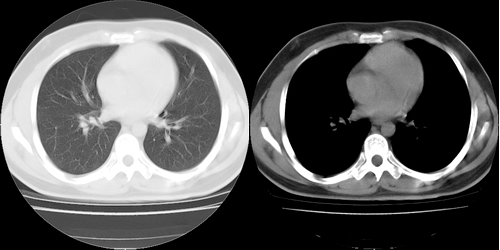

患者 男性 25岁,体检觉得右肺门感觉增大,请会诊,有没有异常?(我科诊断:未见异常)

右肺门增大,气管旁腔静脉后淋巴结肿大

右肺门增大,囊状影与肺动脉分支有关,上叶支气管受压移位。

考虑发生于右肺动脉分支的肺动脉瘤。

鉴别:肺结节病,多侵犯两侧肺门及纵隔淋巴结。

右主支气管及右中叶支气管受压,腔静脉后淋巴结肿大,不知肿块是血管还是淋巴s

没有增强,实在很难说是血管还是淋巴结,纵隔内可见肿大淋巴结,还是先考虑淋巴结吧。我认为

右肺门前方[右侧上叶支气管尖后段分支水平]结节灶,隆突前似有淋巴结显示。结核或肿瘤。建议增强检查

建议增强,右肺上叶前段支气管受压变细,腔静脉后方见肿大淋巴结.考虑结节病或肺门占位.

应该是右肺动脉影,要明确则做个增强扫描。